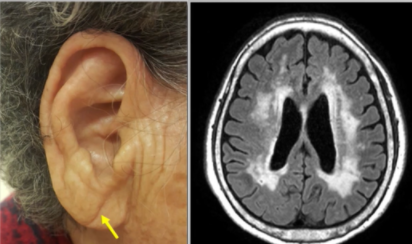

귓볼에 주름이 생기는 원인은 귀의 각 부위 특히 귓볼부위의 미세혈관까지 혈액순환이 원활하지 않음을 보여준다고 합니다. 이와 연관하여 뇌의 작은 혈관들에 혈액순환이 원활하지 않아 막히게 되며 위의 우측 MRI사진의 뇌 중앙부가 하얗게 변성되는 경우가 있다고 합니다.

100% 일치하는 것은 아니지만

귓볼에 혈액순환이 잘 안된다. → 뇌 안의 작은 혈관도 혈액순환이 안될 수 있다.

이렇게 이해하시면 될듯합니다.

귓볼 뿐만아니라 몸 구석구석 뇌 안의 미세한 혈관까지 혈액순환을 시킬 수 있도록 많은 노력을 기울여야 합니다.

※ 귓볼 주름이 심하고, 운동기능 저하 및 기억력이 줄어드는 게 느껴지는 경우 꼭 정밀검사받아보시기 바랍니다.